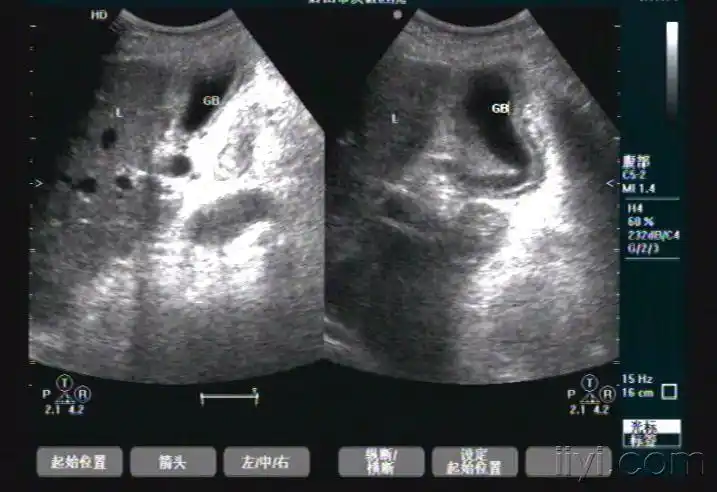

胆囊腺肌症可能,请指教 - 超声医学讨论版 - 爱爱医医学论坛

胆囊腺肌增生病的超声表现

图3-19 胆囊腺肌症(节段型)